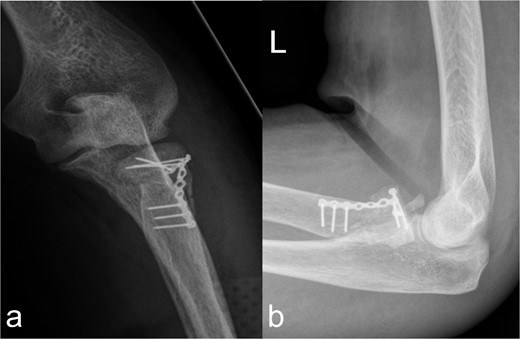

Osteosynthetic treatment via an open approach to the knee joint presented the multifragmentary femoral fracture radiating into the joint with an osseous avulsion of the lateral collateral ligament and posterolateral insertion of the anterior cruciate ligament (Fig. 1b). After reduction of the fracture fragments with temporary fixation using K-wires, an LCP 6-hole plate (Synthes®) was positioned medially and a 7-hole LISS plate (Synthes®) laterally and anchored with multiple screws (Fig. 2a and b). The osseous avulsion of the anterior cruciate ligament was fixed with a 3.5-mm SharkScrew®, the avulsion of the lateral collateral ligament with two FibreWire Loops®.

Treatment patterns of supra-intracondylar multifragment fracture (33C3.2). (a) The anterior-posterior and (b) lateral radiographs show a correct position of the osteosynthesis material with an nearly anatomical fracture position.

In the fractures described, the osteopenic bone texture with rarefied spongiosa, thinning of the cortical bone and dislocated fragments present an intraoperative challenge in achieving a good reduction in an axially correct position and hardware fixation. In order to achieve the best possible primary stability in the acute situation and to minimize the occurrence of secondary fractures, locking plates, screws with different threads, intramedullary nails, wire cerclage, total endoprostheses, and additional PMMA cement augmentation are used [9–14]. In our patient, this was achieved by means of plate osteosynthesis and additional screws. In the complex multifragment fracture of the distal os femoris, lateral and medial plate insertion was performed to achieve sufficient stability (Fig. 2a and b). This minimizes the development of pseudarthrosis, while lateral and medial plate osteosynthesis does not have a negative influence on vascularity [15, 16]. However, even in nonorgan transplanted patients after optimal osteosynthesis of a distal femur fracture, a second surgery is necessary in every eighth patient [17]. In the case of multiple localizations with more complex fracture courses, several operations and follow-up procedures may be necessary. This necessitates extensive postoperative care, especially in organ transplant patients. Chiou et al. [18] report a 62.5 % mortality rate over the course of 1076 days in lung transplant patients after treatment of a fracture of the lower extremity.